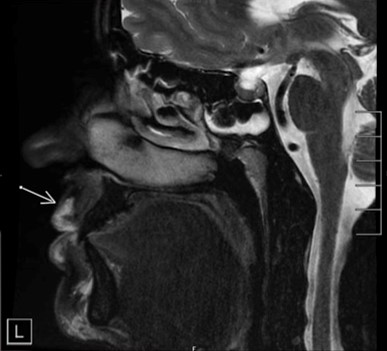

这是一位大约已经打了玻尿酸1-2年的朋友的MRI图像(这图着实有点吓人)

图中箭头指向的白 {MOD}部分就是玻尿酸了,这些玻尿酸旁边的黑 {MOD}区域就是脂肪。

图中,上面箭头指向的是玻尿酸,下面箭头指向的是脂肪。